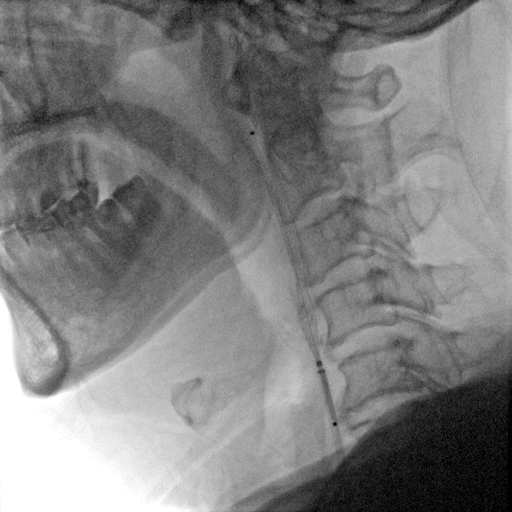

左侧颈总动脉正侧位造影

常规消毒、铺巾后,采用改良Seldinger技术穿刺右桡动脉。

造影导丝和Sim2造影导管将7F EasyRadial™输送导管置于颈内动脉:

路径图下,微导丝越过颈内开口狭窄段达岩骨段,取2.5*15mm 颅内球囊扩张导管送至左侧颈内动脉开口狭窄处给予预球囊扩张成形术。

球囊扩张后狭窄改善。

输送保护伞至颈内动脉C1末端平直段。

沿保护伞导丝送入7.0*50mm Wallstent颈动脉支架至颈内动脉开口处。

准确定位后释放支架。

支架释放后造影显示残余狭窄40%。

再次沿保护伞导丝送入4.0*25mm 颅内球囊扩张导管,越过支架送至颈内动脉开口狭窄最严重处给予球囊后扩张成形术。

术后造影显示支架内无明显残余狭窄,颅内血管无明显栓塞。